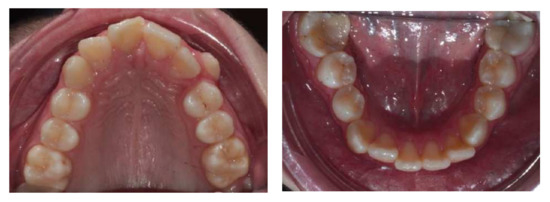

Treatment lasted 26 months. Treatment goals were reached: correction of class II malocclusion was obtained, bilateral molar and canine class I occlusion was achieved, anterior crowding and deep bite were corrected and the smile’s aesthetic was improved.

Figure 8.

Post-treatment models.